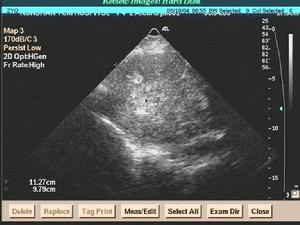

慢性特發性心包積液症慢性特發性心包積液症是一種較常見的臨床表現,尤其是在超聲心動圖成為心血管疾病的常規檢查方式之後,心包積液在病人中的檢出率明顯上升,可高達8.4%。大部分心包積液由於量少而不出現臨床徵象。少數病人則由於大量積液而以心包積液成為突出的臨床表現。當心包積液持續數月以上時,便構成慢性心包積液。導致慢性心包積液的病因有多種,大多與可累及心包的疾病有關。

本病尚缺乏精確而統一的定義。一般以符合下列特徵者歸入本病:①存在大量的心包積液,並已由UCG證實;②心包積液量在觀察期基本保持穩定;③心包積液持續存在至少3個月以上;④病人已被排除任何全身性疾病,而不論該病是否可能與心包積液有關;⑤系統的病因學檢查為陰性。本病有時被稱為“慢性滲出性心包炎”、“慢性特發性心包炎”,但由於在大多數情況下病人不具有心包炎的表現,因而這些命名逐漸避免使用。本病在心包疾病中的發生率約為2%~3.5%。

臨床多通過常規X線胸片檢查發現心影增大,再經UCG和全身系統檢查,以及病因學檢查,排除特異性病變如結核性心包炎、風濕性心包炎等之後可診斷本病。